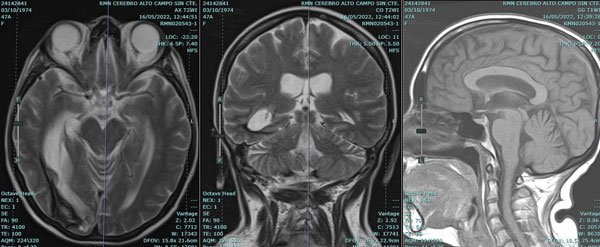

La RMN realizada de inmediato mostró edema cerebeloso y ausencia de compromiso troncal (Figura 8).

Figura 8: RMN y angioRMN: se aprecia edema cerebeloso bilateral, compromiso cerebral a nivel occipital a predominio derecho, balonización del tercer ventrículo y ausencia de oclusiones arteriales.

Finalmente, y luego de 45 días de la PTO inicial, logró derivarse a un centro de rehabilitación. Una RMN de control a los 3 meses mostró secuelas menores a nivel parenquimatoso y ausencia de hidrocefalia (Figura 10). A 8 meses del episodio inicial la paciente es independiente, refiere trastornos mínimos en la memoria anterógrada, y deambula por sus propios medios. Al examen neurológico se constata hemianopsia homónima derecha (Figura 11).

Figura 10: izquierda y centro, RMN de encéfalo control realizada a los 4 meses del episodio de hidrocefalia aguda. Se aprecia la secuela del sangrado a nivel occipital derecho: hipointensidad por hemosiderina y retracción del sector ventricular adyacente. Derecha: secuencia T1 sagital donde se aprecia la normalidad de las estructuras infratentoriales.